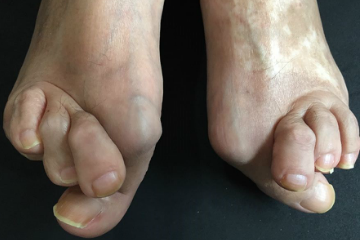

・ハンマートゥ

これらは外反母趾の方に見る外反母趾以外に抱える悩みや症状などです。

外反母趾は足に合わない無理な靴、足に強いる不適切な足の環境の影響を続き発症、悪化を続けます。